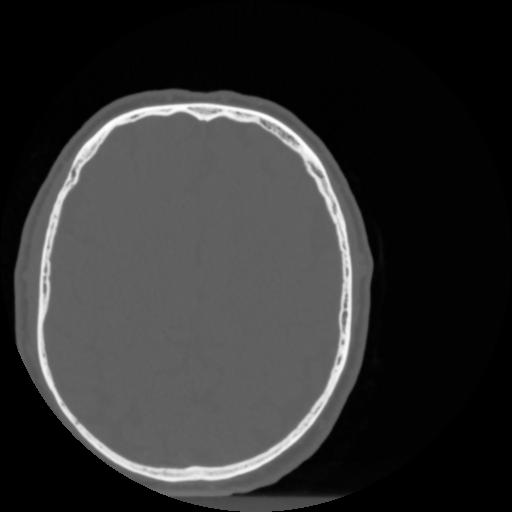

4 CEREBRO,,Vol,0.5,CEREBRO,,